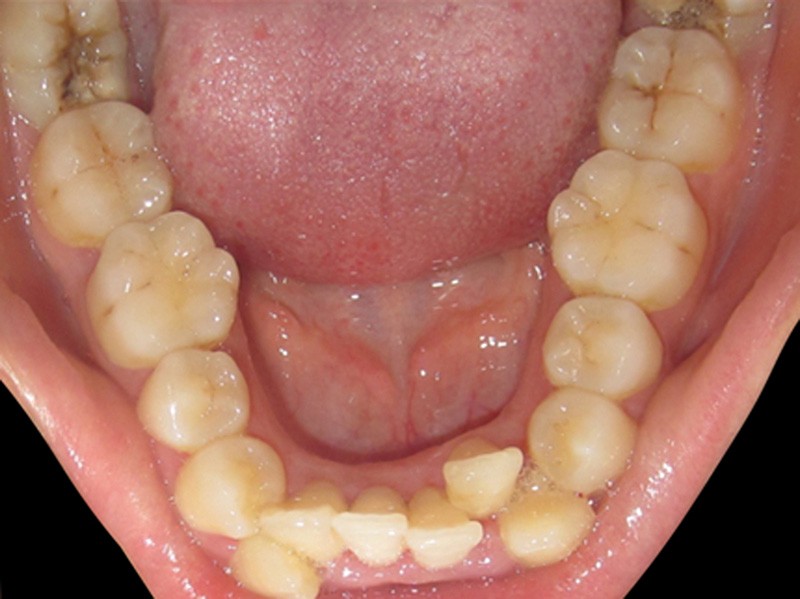

Manque d’espace en distal de la 2e molaire

Il est très important d’évaluer la distance rétromolaire avant l’indication de l’extraction de dents de sagesse incluses pour éviter des extractions abusives et systématiques (manque de bénéfices démontrés et procédures qui ne sont pas sans risques) (fig. 2).